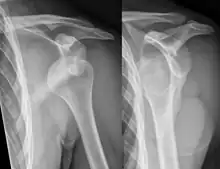

X-ray at left shows anterior dislocation in a young man. X-ray at right shows the same shoulder after reduction and internal rotation, revealing a Bankart lesion and a Hill-Sachs lesion.

In over 95% of shoulder dislocations, the humerus is displaced anteriorly.[7] In most of those, the head of the humerus comes to rest under the coracoid process, referred to as sub-coracoid dislocation. Sub-glenoid, subclavicular, and, very rarely, intrathoracic or retroperitoneal dislocations may also occur.[8]

Anterior dislocations are usually caused by a direct blow to, or fall on, an outstretched arm. The person typically holds his/her arm externally rotated and slightly abducted.

A Hill–Sachs lesion is an impaction of the head of the humerus left by the glenoid rim during dislocation.[6] Hill-Sachs deformities occur in 35–40% of anterior dislocations. They can be seen on a front-facing X-ray when the arm is in internal rotation.[9] Bankart lesions are disruptions of the glenoid labrum with or without an avulsion of bone fragment.